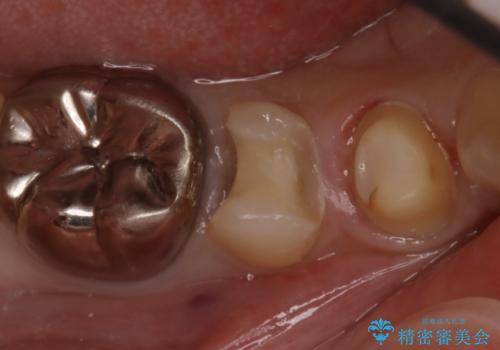

- 右下が痛くて噛めないとの理由で来院された患者様です。レントゲン撮影、歯髄の診断等から、根管治療、歯髄保存療法が必要と判断し、治療後に丈夫で審美性に優れたセラミックインレー、フルジルコニアクラウンを被せました。